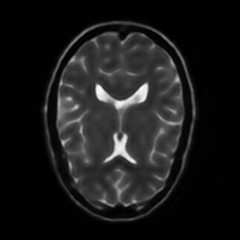

Limited by imaging systems, the reconstruction of Magnetic Resonance Imaging (MRI) images from partial measurement is essential to medical imaging research. Benefiting from the diverse and complementary information of multi-contrast MR images in different imaging modalities, multi-contrast Super-Resolution (SR) reconstruction is promising to yield SR images with higher quality. In the medical scenario, to fully visualize the lesion, radiologists are accustomed to zooming the MR images at arbitrary scales rather than using a fixed scale, as used by most MRI SR methods. In addition, existing multi-contrast MRI SR methods often require a fixed resolution for the reference image, which makes acquiring reference images difficult and imposes limitations on arbitrary scale SR tasks. To address these issues, we proposed an implicit neural representations based dual-arbitrary multi-contrast MRI super-resolution method, called Dual-ArbNet. First, we decouple the resolution of the target and reference images by a feature encoder, enabling the network to input target and reference images at arbitrary scales. Then, an implicit fusion decoder fuses the multi-contrast features and uses an Implicit Decoding Function~(IDF) to obtain the final MRI SR results. Furthermore, we introduce a curriculum learning strategy to train our network, which improves the generalization and performance of our Dual-ArbNet. Extensive experiments in two public MRI datasets demonstrate that our method outperforms state-of-the-art approaches under different scale factors and has great potential in clinical practice.